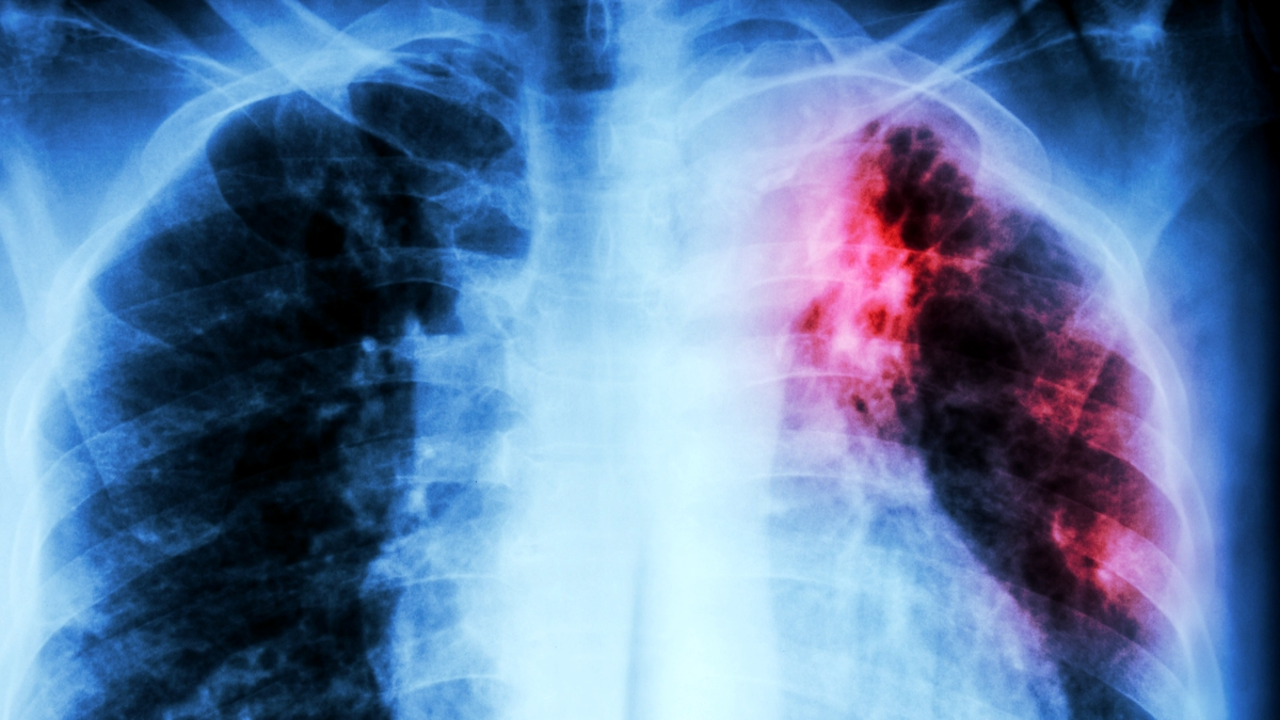

World TB Day: A New Clue Offers Hope Against The Deadliest Infection

Tuberculosis (TB) is on the rise, with the World Health Organization (WHO) calling it a public health crisis and increasingly resistant to antibiotics. Researchers from the University of Sydney have found that three experimental antibiotic compounds, ecumicin, ilamycins, and cyclomarins, can disrupt the protein recycling system of Mycobacterium tuberculosis, the bacterium that causes TB. They found that each compound disrupts the system in a different way, causing widespread imbalances across the whole bacterium. The study suggests that these compounds could potentially be used as effective treatments against TB, which is currently claiming over a million lives a year.